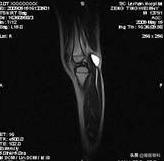

MRI 检查是目前公认的诊断膝关节肿物并评估膝关节病变的金标准。核磁影响不仅能准确显示囊肿,了解囊肿开口与关节腔及周围结构的关系,还能观察到其他影像学方法不能显示的引起囊肿的关节原发病变,如:半月板撕裂、软骨损伤、韧带损伤情况等情况,对于指导手术方案和评估预后有重要意义。